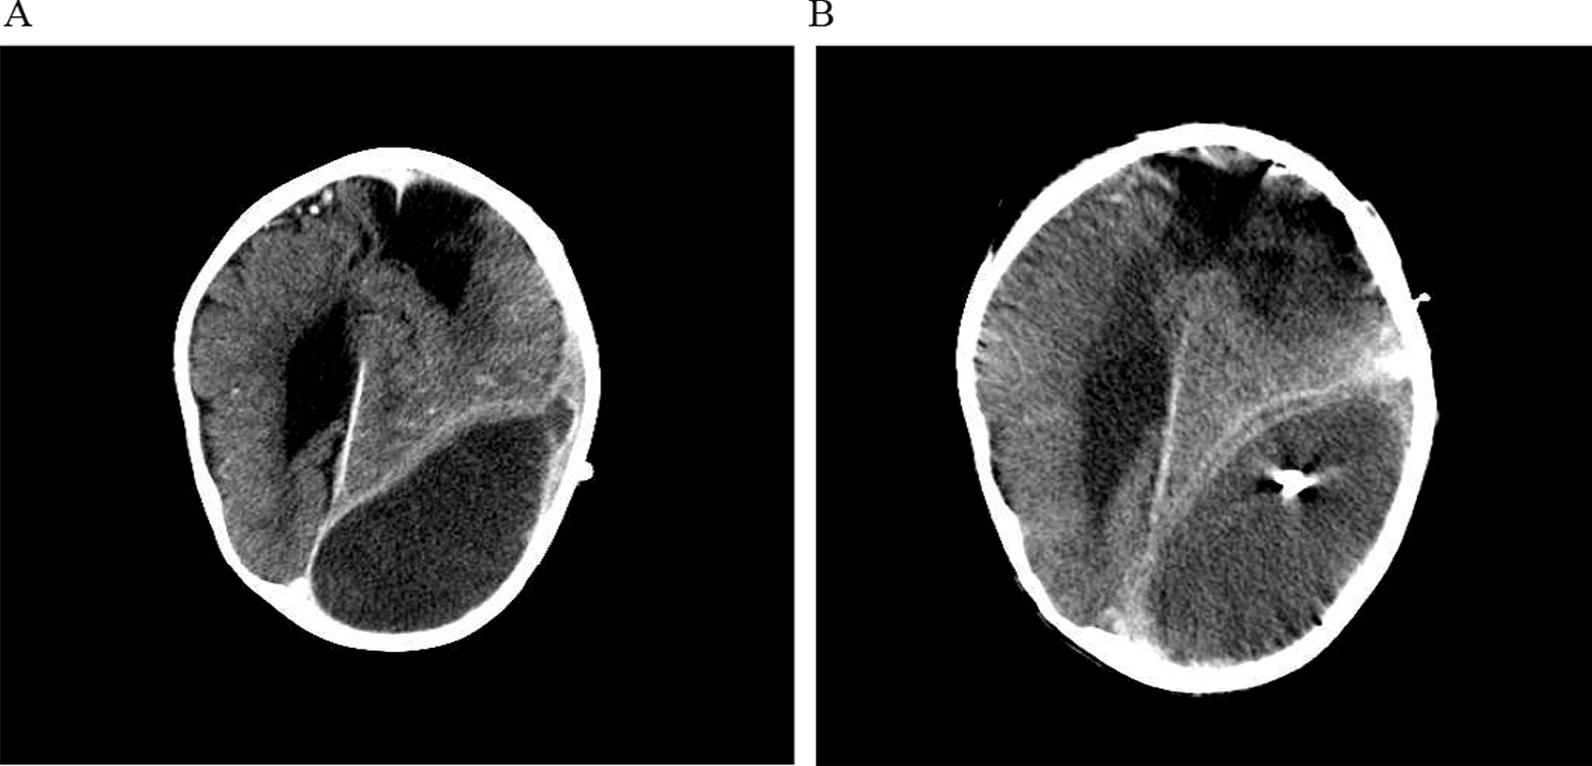

We described a 2-year old boy with lobar holoprosencephaly presenting with subdural hygroma following head trauma. C. jejuni infection was confirmed from a subdural hygroma sample by culture as well as by DNA sequencing of a broad range 16S rDNA PCR product. Cerebrospinal fluid from the ventriculoperitoneal shunt remained sterile. Combined neurosurgical and antimicrobial treatment led to complete recovery. Review of the literature showed that the most common manifestation of Campylobacter central nervous system infection is meningitis, mostly in neonates, and subdural hygroma infection was described for only one case.

我们描述了一例 2 岁男孩,因头部外伤后出现硬脑膜下积脓,伴有脑裂畸形。空肠弯曲菌感染通过培养和广泛的 16S rDNA PCR 产物的 DNA 测序从硬脑膜下积脓样本中得到证实。脑室-腹腔分流的脑脊液仍无菌。联合神经外科和抗菌治疗后完全康复。文献回顾表明,弯曲菌中枢神经系统感染最常见的表现是脑膜炎,主要发生在新生儿,仅有一例硬脑膜下积脓感染的病例描述。